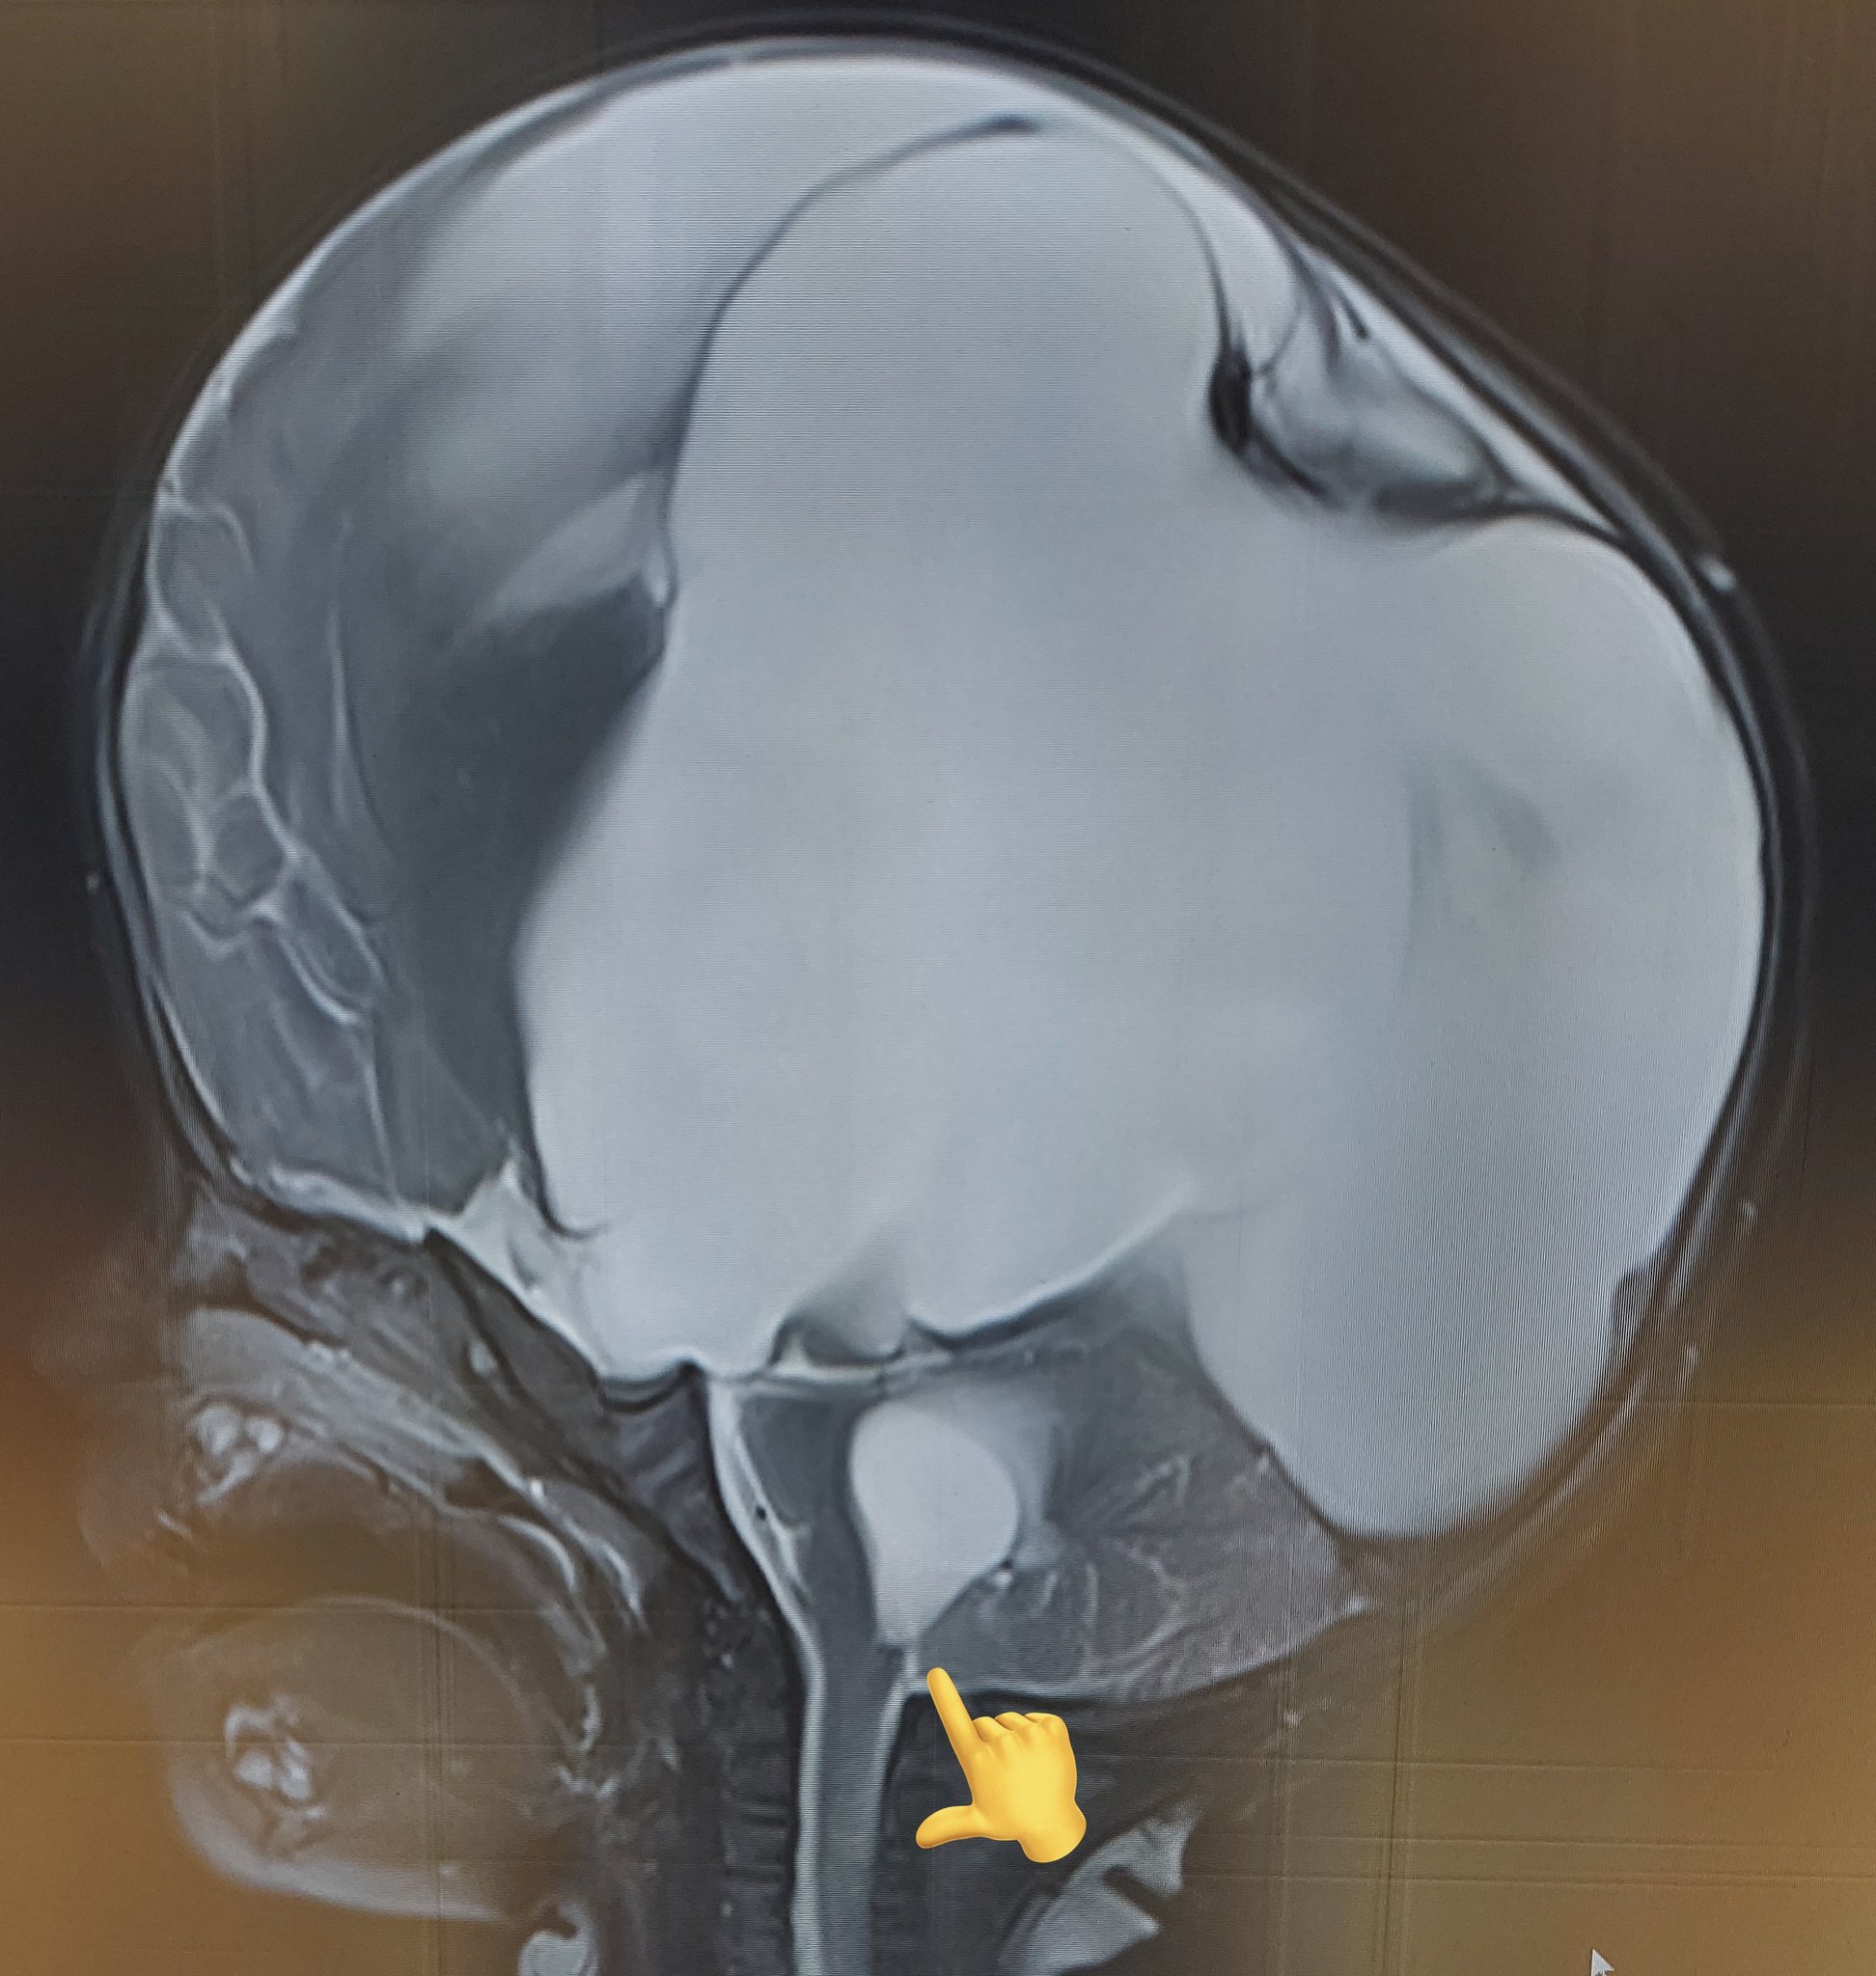

From twitter.com

Rajesh S on Twitter "9 month old kid with enlarging head size🙇♂️ ☣ Torch Infection Hydrocephalus congenital torch infections comprise a group of diseases that affect the fetus and the newborn. Infections acquired in utero or during the birth process are a significant cause of fetal and. the torch infections include causative organisms toxoplasma gondii, rubella virus,. in case of fetal infection, early diagnosis and prolonged postnatal treatment improve children’s prognosis and consist. Torch Infection Hydrocephalus.

Rajesh S on Twitter "9 month old kid with enlarging head size🙇♂️ ☣ Torch Infection Hydrocephalus torch is an acronym that denotes a chronic nonbacterial perinatal infection. the torch infections include causative organisms toxoplasma gondii, rubella virus,. in case of fetal infection, early diagnosis and prolonged postnatal treatment improve children’s prognosis and consist of. congenital torch infections comprise a group of diseases that affect the fetus and the newborn. It stands for. Torch Infection Hydrocephalus.